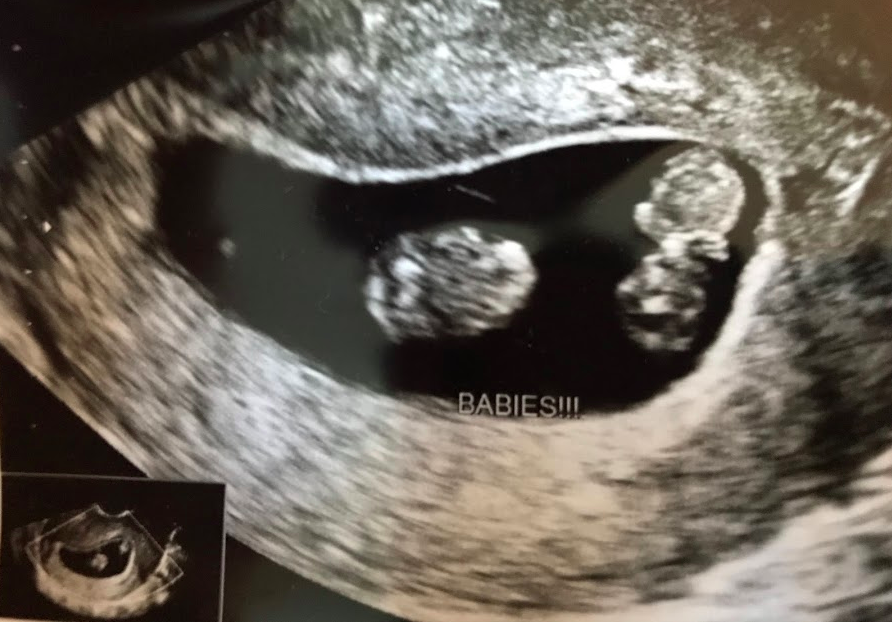

• @xxkberxx congrats so glad I got some twin mama counterparts!